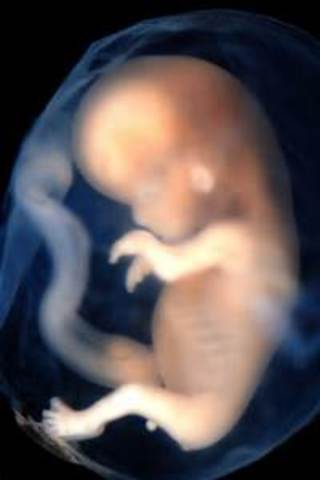

• Once Embryo, Now Fetus

Ears and nose can are developed and fingerprint formation is evident.

• Neurons Multiply

The fetus much resembles a newborn already. The brain is multiplying at a rapid rate of 250,000 cells per minute.

• Finger and Toenails

Along with fingernails and toenails, the fetus now has a facial profile. fetus is around 2.5 inches long now.